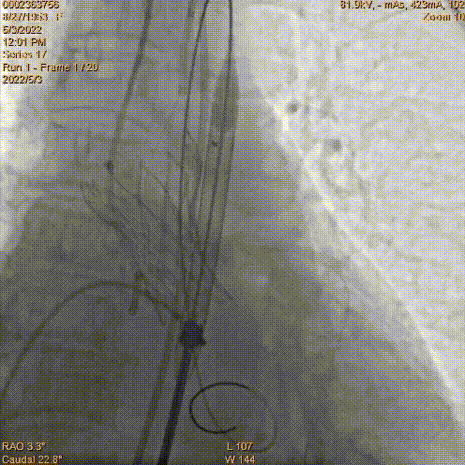

主入路穿刺

主动脉根部造影

导丝跨瓣

球囊预扩,左冠脉血流明显减慢,远端显影不清

瓣膜定位

工作位造影